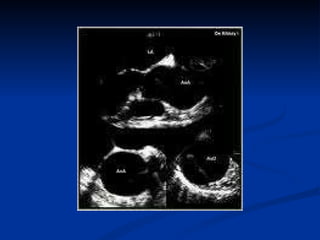

TTE Indicated as an initial test if patient is very unwell and other modalities of imaging not readily available Can be performed bedside Can detect intimal flap and AR Limitation : No information beyond aortic root and early part of proximal aorta

TTE Indicated asan initial test if patient is very unwell and other modalities of imaging not readily available Can be performed bedside Can detect intimal flap and AR Limitation : No information beyond aortic root and early part of proximal aorta